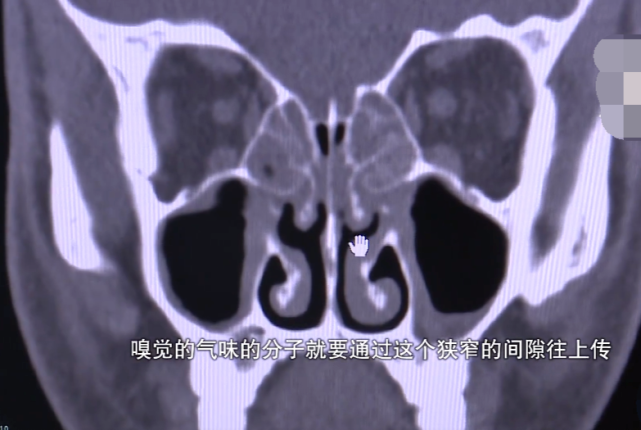

众所周知,鼻窦炎是鼻腔、鼻窦内的炎症。鼻窦炎的典型症状是鼻塞鼻堵,打喷嚏,流鼻涕,但为什么还会造成嗅觉失灵?

鼻窦炎会导致鼻粘膜充血肿胀,从而堵塞了鼻腔嗅觉分子进入的通道,嗅觉分子不能够从鼻腔上传至大脑,最后导致嗅觉失灵。